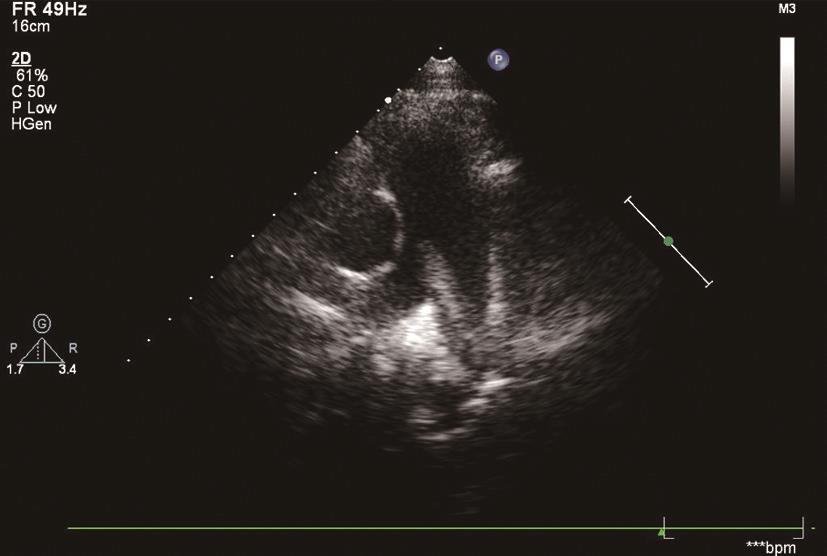

2.间接征象是由于右心室负荷增加所致。①栓子栓塞肺小动脉,右心室充盈压上升,致右心室扩大(图6-1-2),室间隔左移,左心室内径减小;②因右心室收缩负荷过重引起右心室游离壁运动减弱;③肺动脉高压及不同程度三尖瓣反流;④还有肺动脉血流曲线形态的改变。射血前期/射血期(RPEP/RVET)比值增大 >0.3等。仅凭间接征象不能直接诊断肺栓塞,但对于已确诊的肺栓塞患者,通过间接征象,通过超声评估右心室功能不全及血流动力学紊乱,对于治疗的选择、预后的判断具有极其重要的意义。肺栓塞的超声间接征象可以提示诊断,并可在同急性心肌梗死、主动脉夹层动脉瘤、室间隔穿孔等心血管急症的鉴别中发挥重要作用。

图6-1-2 胸骨旁左心室长轴切面显示右心室增大